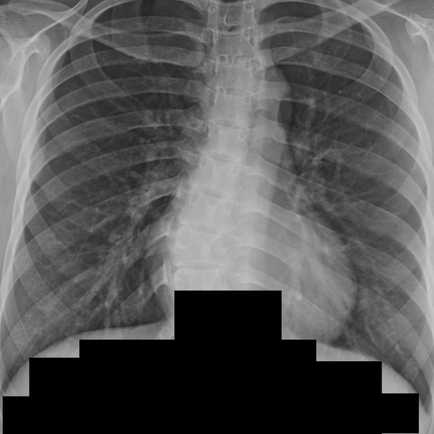

흉수를 동반한 다수의 결절성 침윤, 속립성 결핵 vs. 림프관성 암종증 - 동대문구 답십리, 전농동, 우리안애 우리안愛 내과

호흡기

2025년 1월 27일

1분 분량